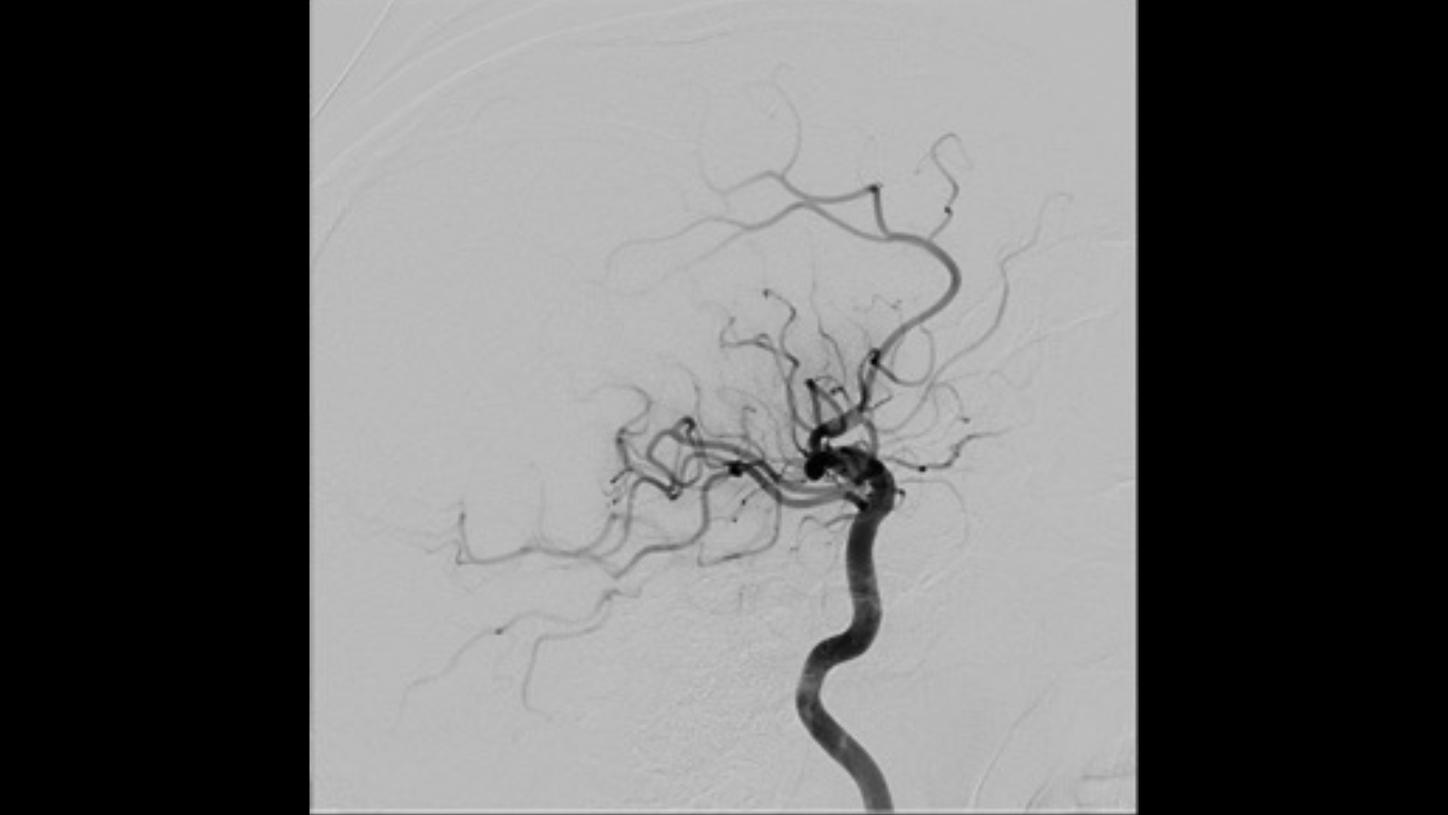

AP projection

AP projection Lateral projection

Lateral projectionFollow-up DSA to visualize treatment success

AP projection

AP projection Lateral projection

Lateral projectionFollow-up DSA to visualize treatment success

AP projection

AP projection Lateral projection

Lateral projection